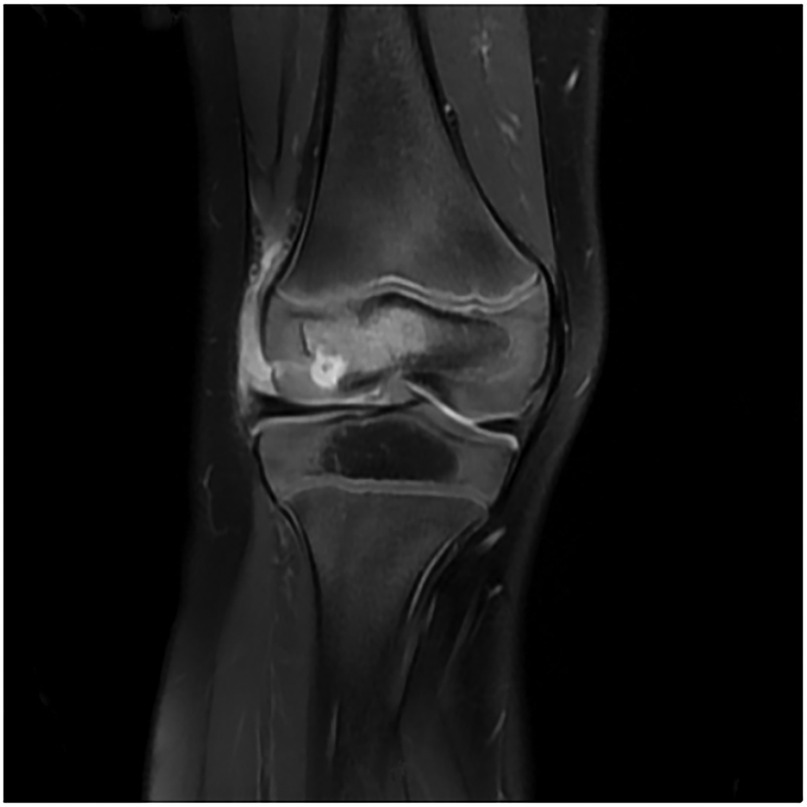

Diagnosis of Salmonella enterica-Induced Septic Arthritis in a Healthy Child Using Metagenomic Next-Generation Sequencing: A Case Report

Salmonella enterica-induced arthritis frequently manifests in children with malignancies, sickle cell disease, immunodeficiency, or undergoing immunosuppressive therapy; however, its incidence in healthy children is rare. Here, we present a case of septic arthritis resulting from S. enterica infection in a previously healthy child, diagnosed utilizing metagenomic next-generation sequencing (mNGS). This case underscores the utility of mNGS in the clinical identification of S. enterica arthritis. Particularly in scenarios where the causative pathogen remains unidentified, mNGS emerges as a pivotal adjunctive diagnostic modality for uncommon pathogens.